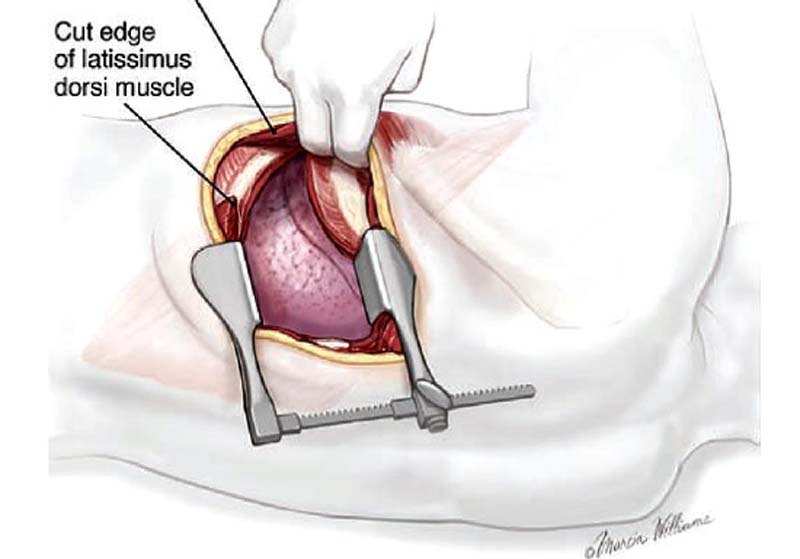

ทั้งนี้ การรักษาโรคปอดและโรคในทรวงอกที่ผ่านมาในอดีต เป็นการผ่าตัดแบบเปิดแผล จะมีแผลผ่าตัดประมาณ 2-3 แผล โดยแผลแรกสำหรับกล้องส่อง แผลที่สองสำหรับอุปกรณ์ดึงรั้ง แผลที่สามสำหรับอุปกรณ์ผ่าตัดและอุปกรณ์ตัดเย็บ โดยแผลจะมีขนาด 3-4 เซนติเมตร โดยหลักการผ่าตัดคือ ให้ตำแหน่งกล้องอยู่บริเวณชายโครงช่องกระดูกซี่โครงที่ 7-8 ส่วนตำแหน่งแผลผ่าตัดหลักและแผลสำหรับอุปกรณ์ช่วยดึงจะอยู่ช่องกระดูกซี่โครงที่ 4-6 บริเวณด้านหน้าและด้านหลัง ทำให้แผลผ่าตัดต้องผ่าช่องซี่โครงหลายช่อง ปกติแล้วคนเราจะมีเส้นประสาทอยู่ใกล้บริเวณขอบล่างของกระดูกซี่โครงแต่ละซี่การใส่อุปกรณ์เข้าไปจึงทำให้คนไข้มีโอกาสที่จะเกิดอาการเจ็บแผลหลังผ่าตัดได้จากการระคายเคืองของเส้นประสาทหลายตำแหน่ง

ปัจจุบันมีการพัฒนาแนวทางการรักษาโรคปอดและโรคในทรวงอกด้วยการส่องกล้องแผลเดียว (Video-Assisted Thoracic Surgery : VATS) เป็นการผ่าตัดส่องกล้องอวัยวะในช่องอก โดยใช้เลนส์ยาวร่วมกับอุปกรณ์ผ่าตัดยาวพิเศษ ผ่านช่องระหว่างซี่โครงโดยไม่มีการถ่างขยายซี่โครง ทำให้มีความแตกต่างกับการผ่าตัดในอดีต ทำให้คนไข้มีอาการเจ็บปวดหลังผ่าตัดน้อย ขนาดแผลเล็ก สามารถกลับไปทำงานได้เร็วขึ้น เพราะไม่ต้องมีการตัดกระดูกและระยะเวลาพักฟื้นในโรงพยาบาลเฉลี่ยเพียง 1-3 วัน ซึ่งการผ่าตัดวิธีนี้จะใช้เทคนิคขั้นสูงในการผ่าตัด แพทย์ที่ผ่าตัดต้องมีความชำนาญและประสบการณ์ในการผ่าตัดส่องกล้องชนิด 2 และ 3 แผลมาก่อนโดยคนไข้ที่ได้รับการผ่าตัดชนิดแผลเดียวจะมีอาการเจ็บน้อยกว่าผ่าตัด 3 แผล โดยผลที่ได้จากการผ่าตัดไม่แตกต่างกัน การผ่าตัดส่องกล้องแผลเดียว (VATS) สามารถทำได้ใน 9 โรคที่กล่าวมา ช่วยทดแทนการผ่าตัดเปิดได้เกือบทุกโรคในทรวงอก แต่อาจมีข้อจำกัดในบางโรค เช่น ภาวะมะเร็งปอดระยะลุกลาม ภาวะมะเร็งเยื่อบุช่องอก (Malignant Mesothelioma) ภาวะติดเชื้อในช่องอกเรื้อรัง (Chronic Empyema Thoracis) เป็นต้น โดยแนวทางการรักษาขึ้นอยู่กับเทคนิคและประสบการณ์ของศัลยแพทย์ผู้ผ่าตัดเป็นผู้ตัดสินใจ